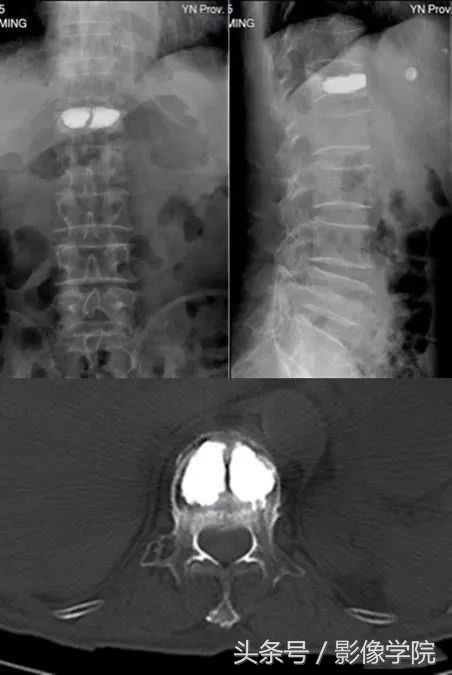

后凸成形术是在经皮椎体成形术的基础上,先用特制的气囊将压缩椎体复位,然后在低压下注入骨水泥,相比PVP可以明显减少渗漏,具有增强稳定性、止疼、恢复身高的优点。

病例演示:老年女性患者,轻微外伤后出现胸背部疼痛不适

MRI提示胸12椎体新鲜骨质疏松性压缩骨折,诊断明确后局部麻醉下行经皮椎体后凸成形术(PKP)

术后即刻患者胸背部的疼痛明显缓解,床上可自由翻身,2小时后下地自由活动,疼痛明显减轻,术后3天患者即可出院。